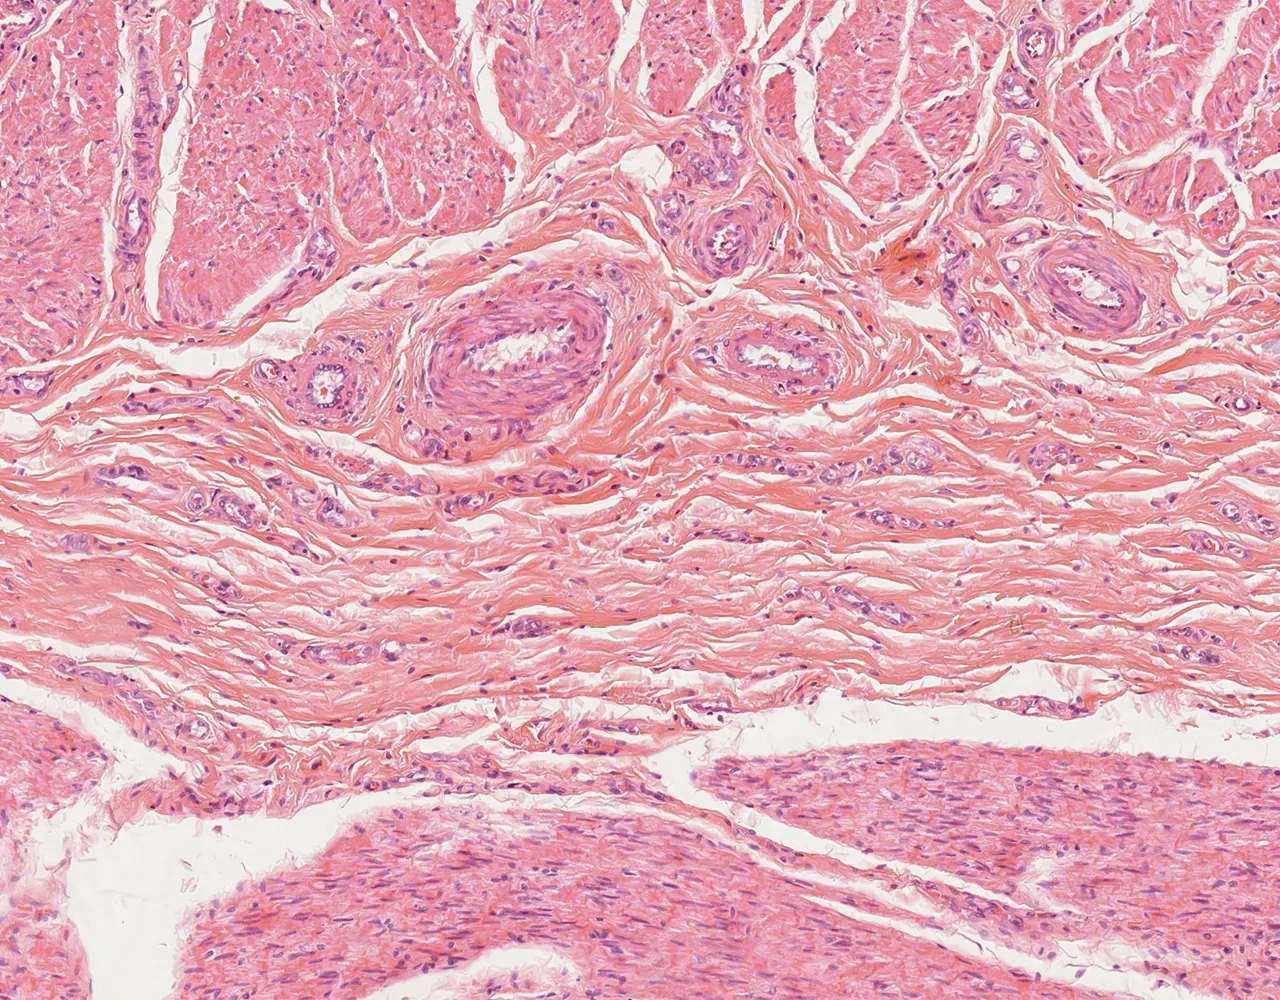

- Microscopically, the esophagus is composed of four layers: mucosa, submucosa, muscularis propria, and adventitia.